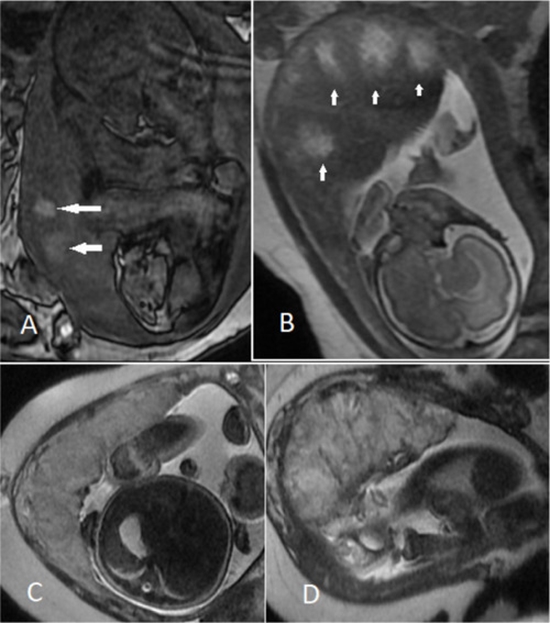

Purpose: We aimed to provide diagnostic models based on different parameters of placental magnetic resonance imaging (MRI) to detect intrauterine growth restriction (IUGR), as well as the severity of placental insufficiency.

Material and methods: We included 44 foetuses with appropriate weight for gestational age (AGA) and 46 foetuses with documented IUGR, defined as the estimated foetal weight (EFW) below the 10th centile. Using Doppler ultrasound, IUGR cases were divided into 2 groups: 1) IUGR with severity signs: EFW < 3rd centile, or cerebroplacental ratio < 5th centile, or abnormal umbilical/uterine artery pulsatility index; and 2) non-severe IUGR without any of this criterion. For all these participants, placental MRI was performed in the third gestational trimester, and its parameters were compared between AGA and IUGR, as well as between the severe and non-severe IUGR groups. Two diagnostic models consisting of significant predictors were developed, and their performance was investigated with accuracy metrics.

Results: The severity signs were detected in 25 (54.3%) IUGR cases. The diagnostic model for the differentiation of IUGR from AGA revealed an acceptable performance (area under the curve [AUC] of 0.749) and consisted of 2 variables: 1) the largest size of infarct ≥ 25 mm (odds ratio [OR] = 5.01, p = 0.001), and 2) thickness : volume ratio ≥ 0.043 (OR = 3.76, p = 0.027); while, the logistic regression model for detection of the severity signs was even better, with AUC = 0.862, and comprised of 2 predictors: 1) placental infarct percent ≥ 10% (OR = 26.73, p = 0.004), and 2) placental globular shape (OR = 5.40, p = 0.034).

Conclusions: Placental MRI parameters can differentiate IUGR from AGA, and more precisely, assess the severity of placental insufficiency in IUGR foetuses.